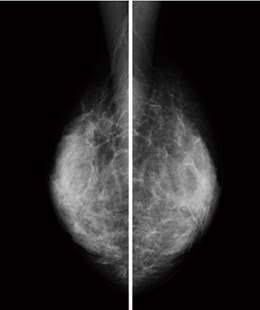

症例画像(乳房厚32mm,平均乳腺線量0.50mGy)

FFDMの画素サイズは,各社から50,70,85,100μmと,さまざまなタイプが発売されている。角田医長は,本院では異なる画素サイズの画像が混在している環境で読影を行っている。角田医長は,「マンモグラフィ検診精度管理中央委員会は5MPのモニタで読影することを推奨しています。100μmと50μmではピクセル等倍表示は違ってくるので,画素サイズに適した拡大率には注意が必要ですが,読影の手順や方法の基本は同じです。画素サイズだけに気を取られずに,装置とビューワをどのように組み合わせるかが重要です」と話す。

MicroDoseで撮影した画像は,コンソールのモニタ(1MP)で確認後,検像端末とクリニック内のマンモグラフィ専用ビューワに送られ,検像画像を本院,予防医療センター,クリニックの統合サーバに送信している。

「現在,高濃度乳房における画像については,満足していない点もまだ見られます。これから,日本人女性により適した画質に改良していくことが,1号機導入施設の役割だと思います。また,読影をする立場からすると,最初に上がってくる初期表示をより良くし,読影医の負担を軽減できるようにしたいですね。メーカーとも協力し,被ばくが少ないメリットを生かしながら,より高い画質を求めていきます」